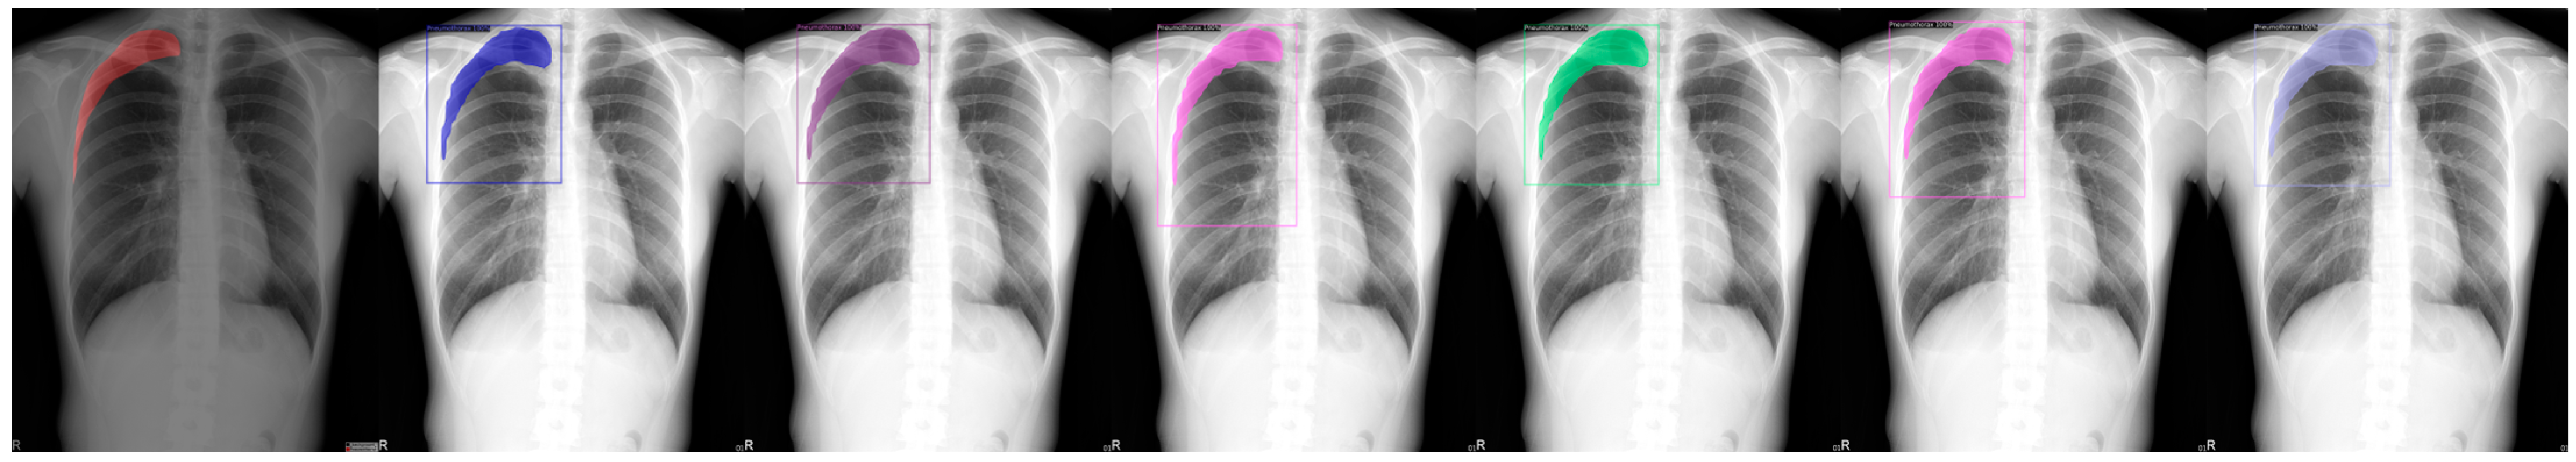

This research project aims to build a usable X-ray images lung disease detection system. Our dataset consists of over 8000 X-ray images, with more than 1000 of them from pneumothorax patients. In this project, we utilized a software called LabelMe [24], as shown in Figure 1. LabelMe annotation project is a standard software that is used to annotate interest segments from a given image and to classify those said segmented images.

Figure 1.

LabelMe in action on annotating pneumothorax, with the red shadow marking the ground truth of the affected area of the pneumothorax disease.